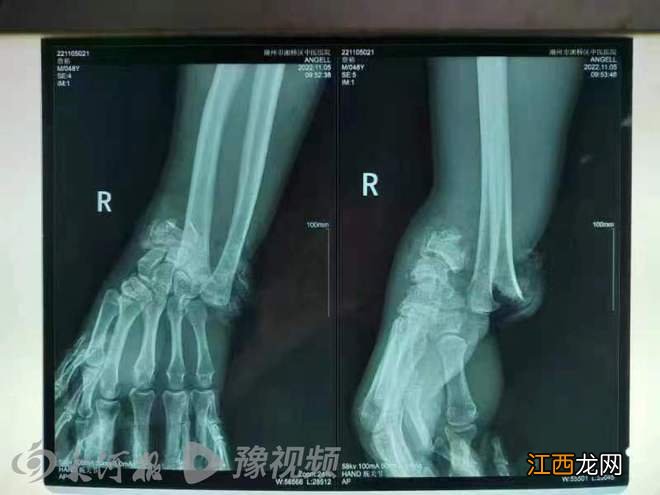

文章插图

三轮车驾驶员X光片